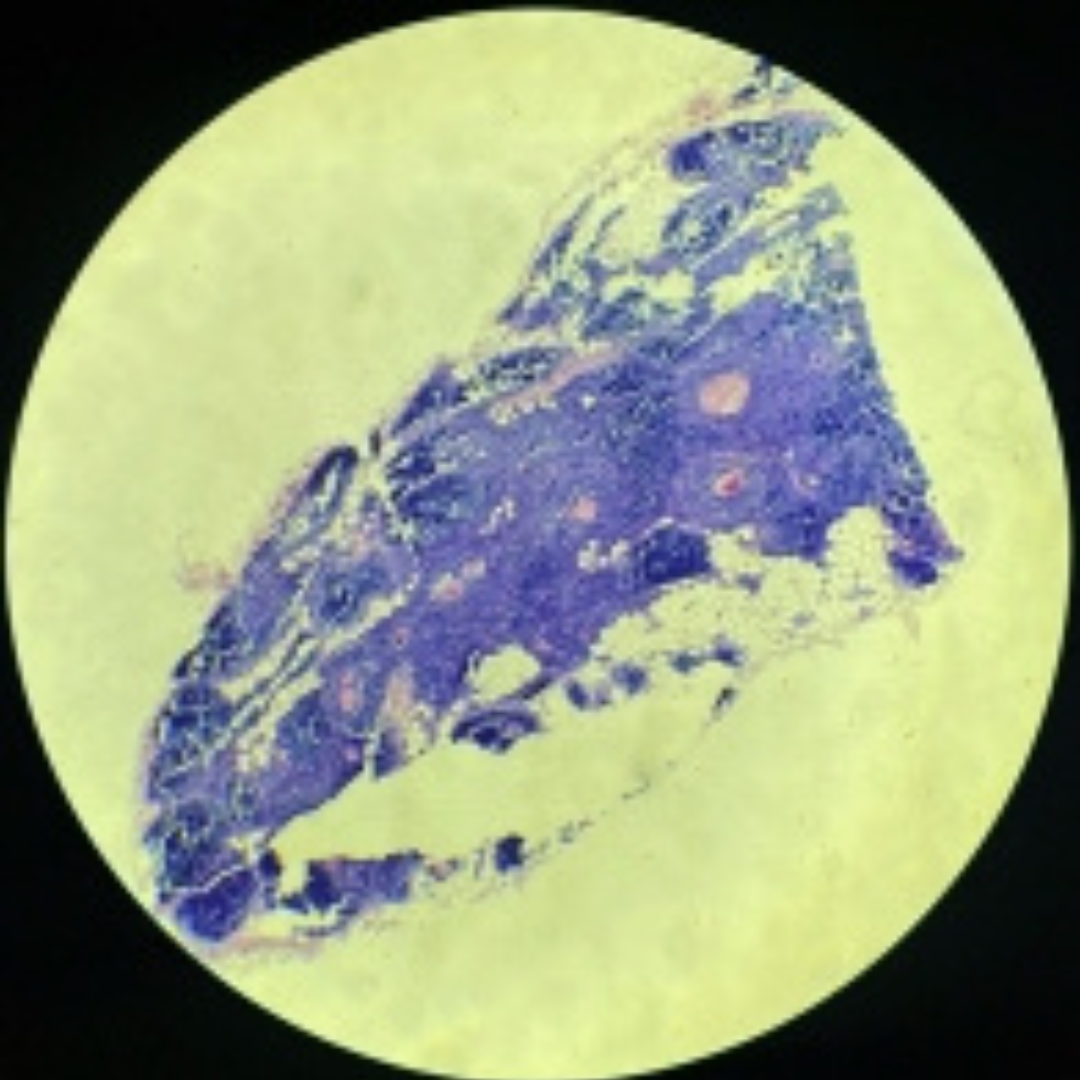

Thymus

33

New cards

Thymus

34

New cards

Thymus